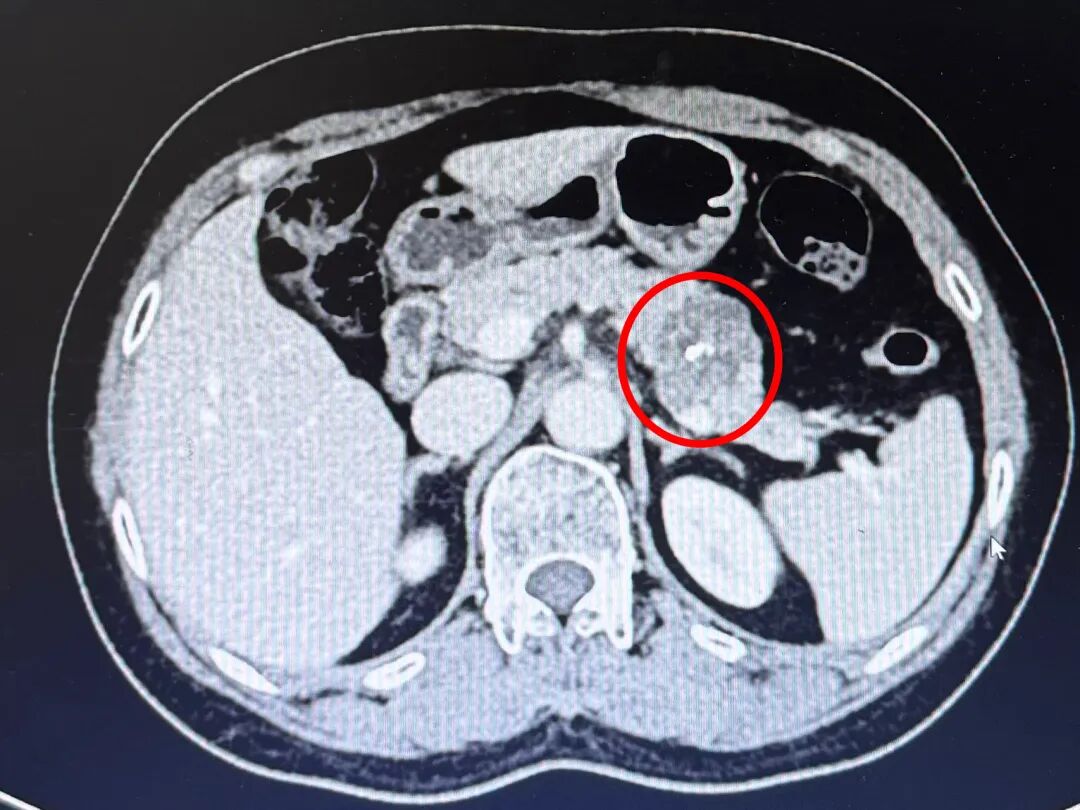

基本资料:患者为58岁女性,因“体检发现胰腺占位1月”入院,身体状况良好,BMI:22.5,CA199:5.5,增强CT提示胰尾3.5cm混杂低密度灶。

术前影像学评估及规划:MRI上呈多囊型、“蜂窝征”,中央钙化,我的初步印象符合SCN浆液性囊腺瘤“奶奶瘤”的表现。做Kimura还是Warshaw?CT增强看到肿瘤几乎将脾动静脉完全“吃”进去,但肿瘤距离LGA和SA在脾门的汇合点有一定距离。我知道Kimura很好,但在腔镜下剥离脾静脉带给我的多是一些不太美妙的回忆,而且从我做Warshaw的经验看,患者普遍恢复得不错。